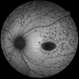

- Choroidal nevus

- Dr. Apoorva Jadhav, National Institute of Ophthalmology, Pune. India.

Fundus camera

Zeiss Clarus 500 - Description

- Color fundus photograph of the left eye of a 55 year old male showing large choroidal nevus.